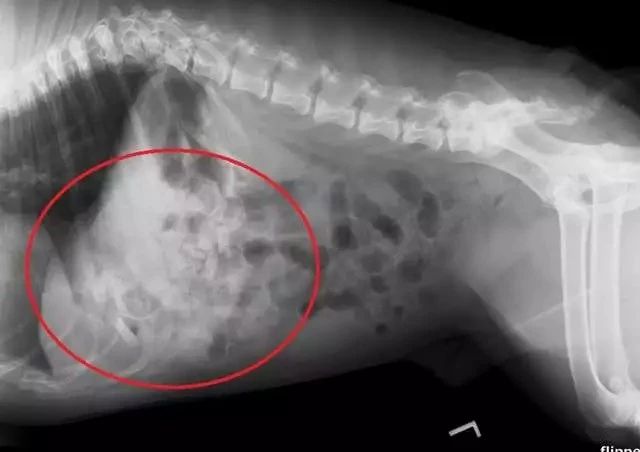

另一位铲屎官家的英斗从4月份开始经常出现呕吐现象,但一直没有找出原因。刚开始主人以为吃坏肚子了,从宠物诊所拿了一些药......没有起到丝毫作用。

原本活泼好动的狗子,变得嗜睡、无精打采,甚至拒食。主人这才意识到情况有些严重,带着狗狗到宠物医院进行了检查。

在X光照射下才终于查明病因,狗狗胃中塞满了异物。

医生立即安排了手术,结果让人大吃一惊:竟从狗子的胃里取出了19个安抚奶嘴。主人从来没有注意到安抚奶嘴居然被狗狗偷吃了这么多。